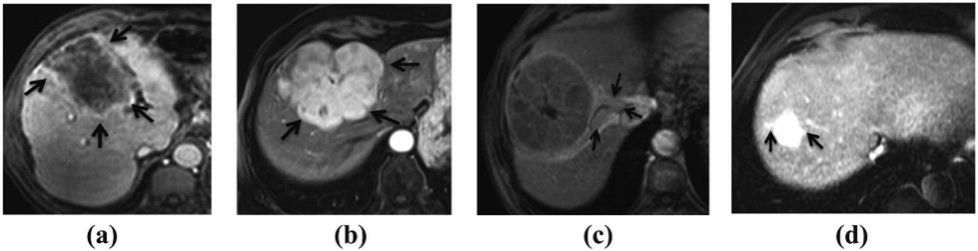

图1: MVI发生时器官产生的不同表现:(a)肿瘤包膜的外观、(b)肿瘤边缘、(c)瘤周异常增强和(d)外周动脉增强。

原发性肝癌是主要的全球健康威胁之一,在最常见和最致命的恶性肿瘤中排名第六。肝癌早期症状一般较为隐匿,不易被察觉,大约70%的肝癌病例只有在中期或晚期才能够被诊断出来。尽管外科和内科治疗都有一定效果,但肝癌患者的5年生存率仍低于30%。虽然肝切除术是早期肝癌的关键治疗方法,但是术后肿瘤复发率仍然较高。微血管侵犯(MVI)是微血管中存在的癌性血栓(如图1所示),肉眼无法检测到,但在显微镜下可识别。MVI可独立预测肝癌切除术后早期复发及预后不良,准确的术前MVI评估对于指导肝癌患者的治疗决策和提高生存率至关重要。